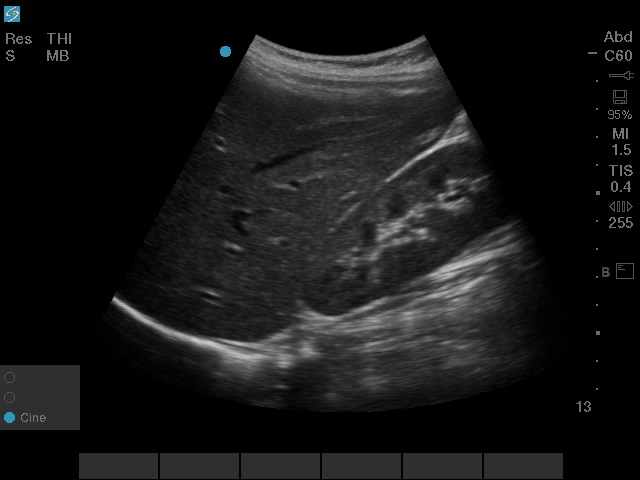

Cuadrante superior derecho (CSD)

Imagen del cuadrante superior derecho (CSD) mediante rC60xi